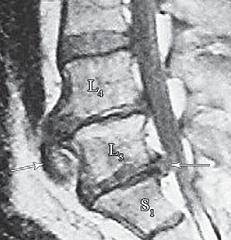

На МРТ № 15 наблюдается двухсторонняя экстрафораминальная грыжа межпозвонкового диска (расположенная за межпозвонковыми отверстиями) На МРТ № 16 наблюдается медиолатеральная протрузия и вентральная грыжа межпозвонкового диска

На МРТ № 17 наблюдается вентральная грыжа межпозвонкового диска в сегменте ThXII-LI с выраженными спаечными процессами на этом уровне, с вовлечением в данный процесс брюшной аорты В сагиттальной плоскости (вертикальный срез) грыжи межпозвонковых дисков разделяют на вентральные, дорсальные, краниальные и каудальные. МРТ № 18